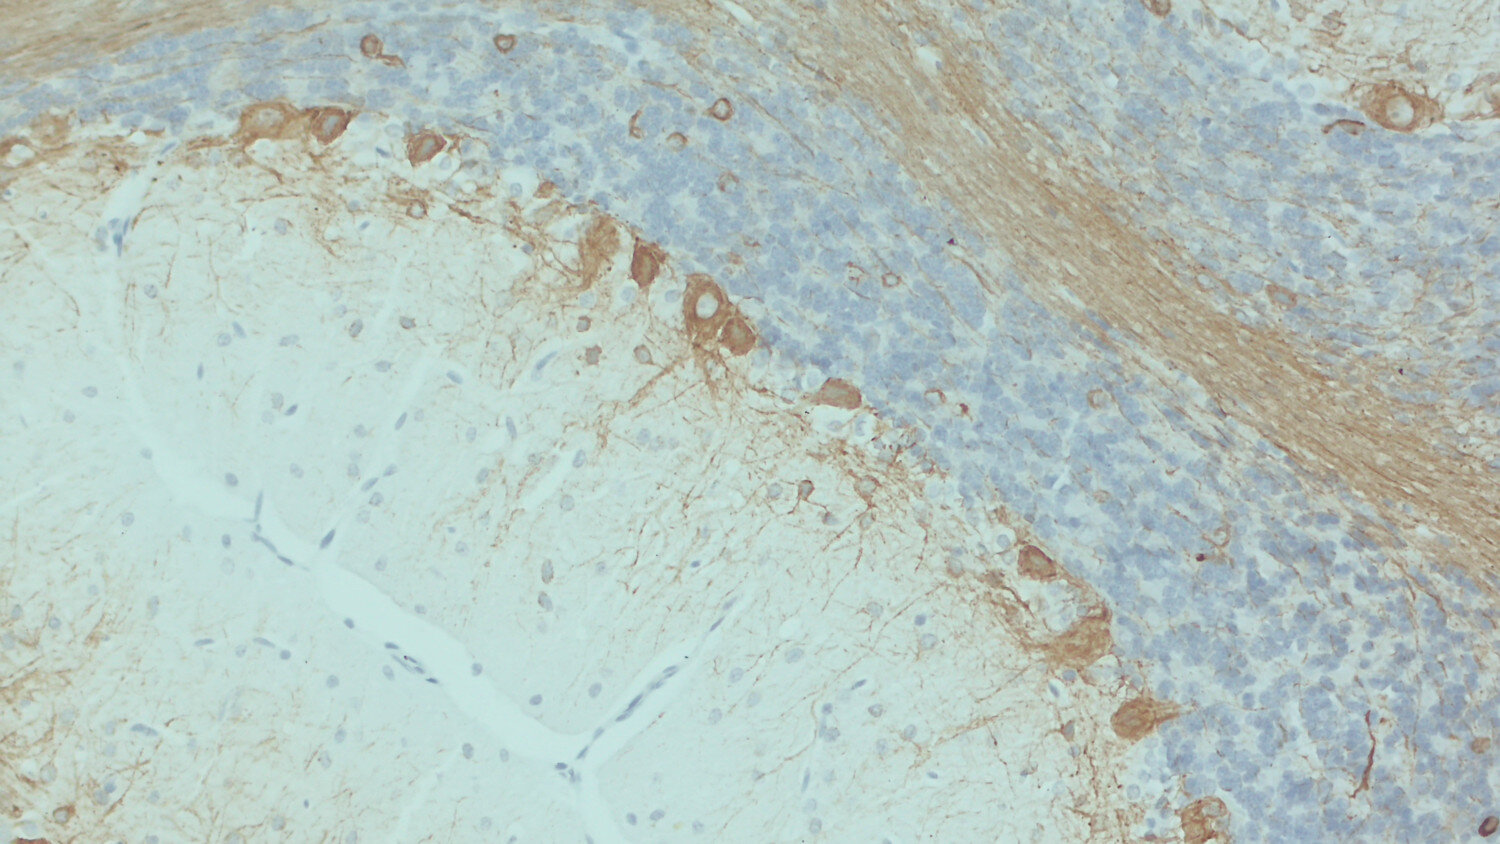

IHC: 1 : 500 gallery

IHC-P: 1 : 100 up to 1 : 1000 gallery

Immunohistochemistry (IHC-P) of formalin fixed, paraffin embedded (FFPE) tissue (some antibodies require special antigen retrieval steps, please refer to the ”Remarks” section). Immunoreactivity is usually revealed by fluorescence or a chromogenic substrate.